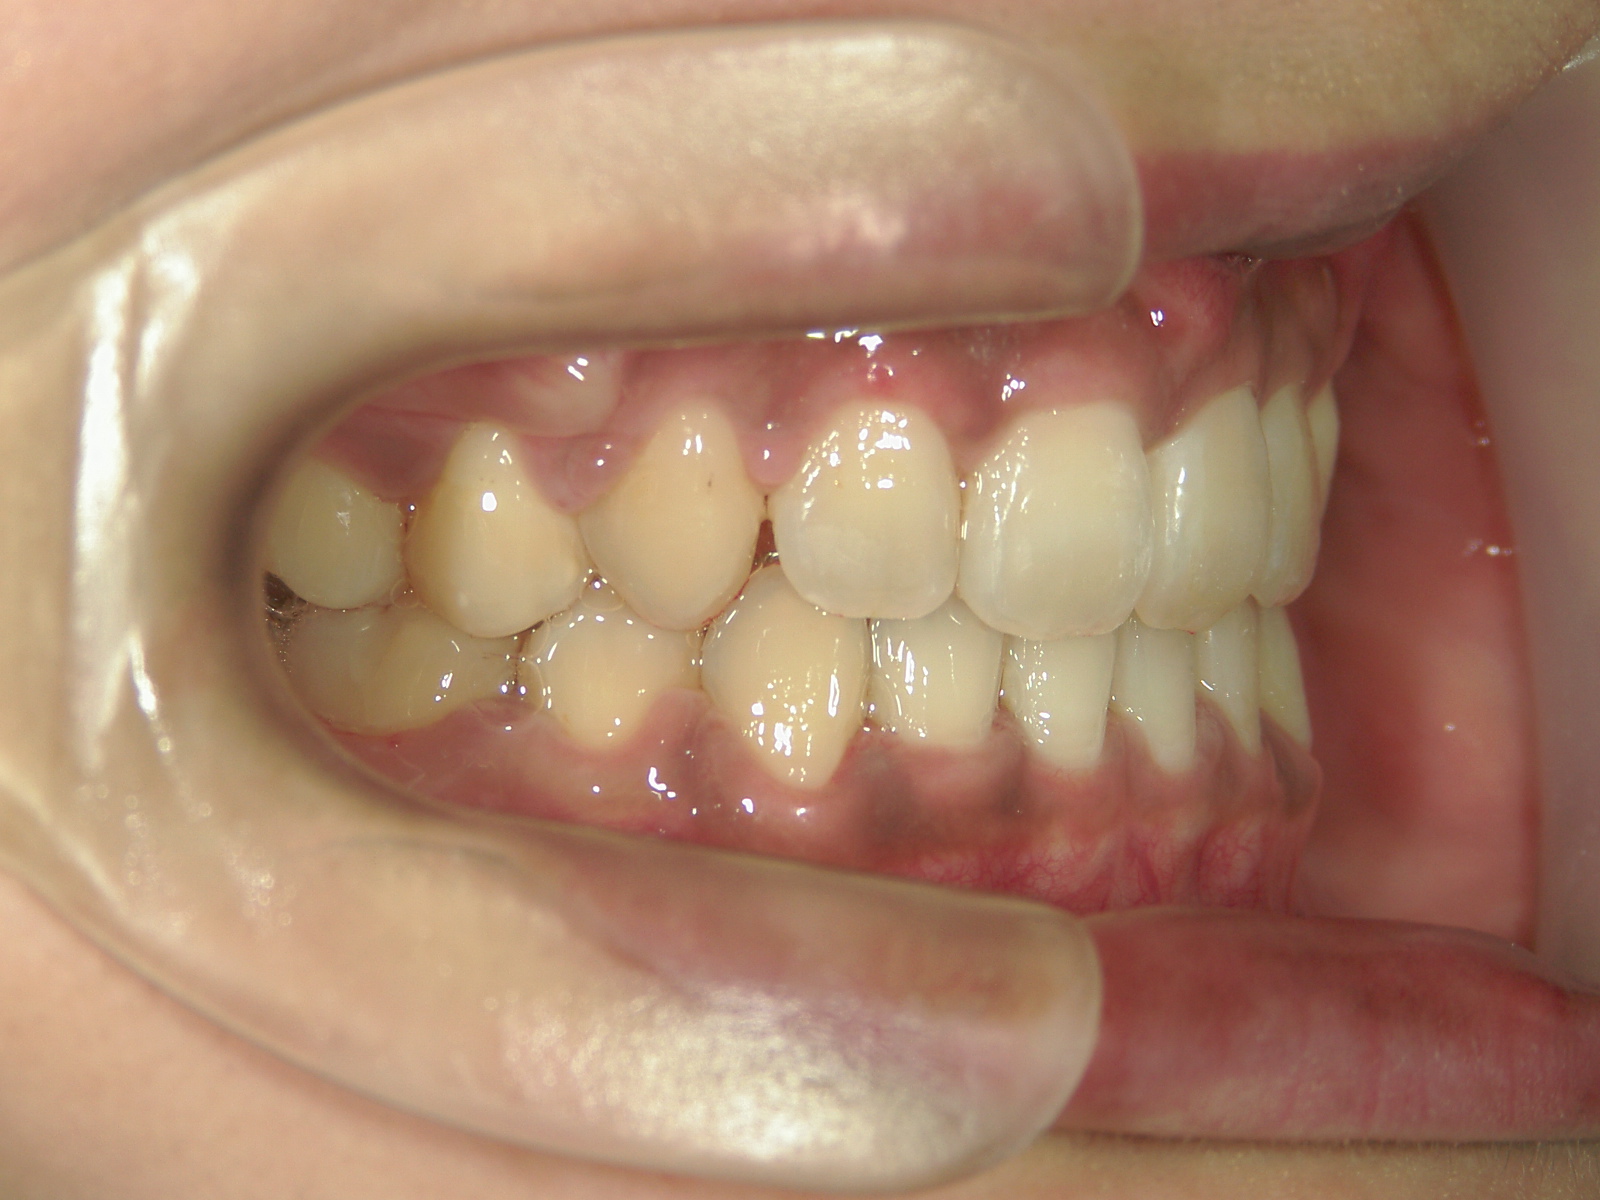

全顎ワイヤー矯正 症例(6)

Ⅱ級ゴム・ミニインプラントを併用

②Ⅱ級ゴムを併用し、隙間を閉鎖しました。

カテゴリー : ガタガタ(叢生) , 噛み合わせが深い(過蓋咬合)